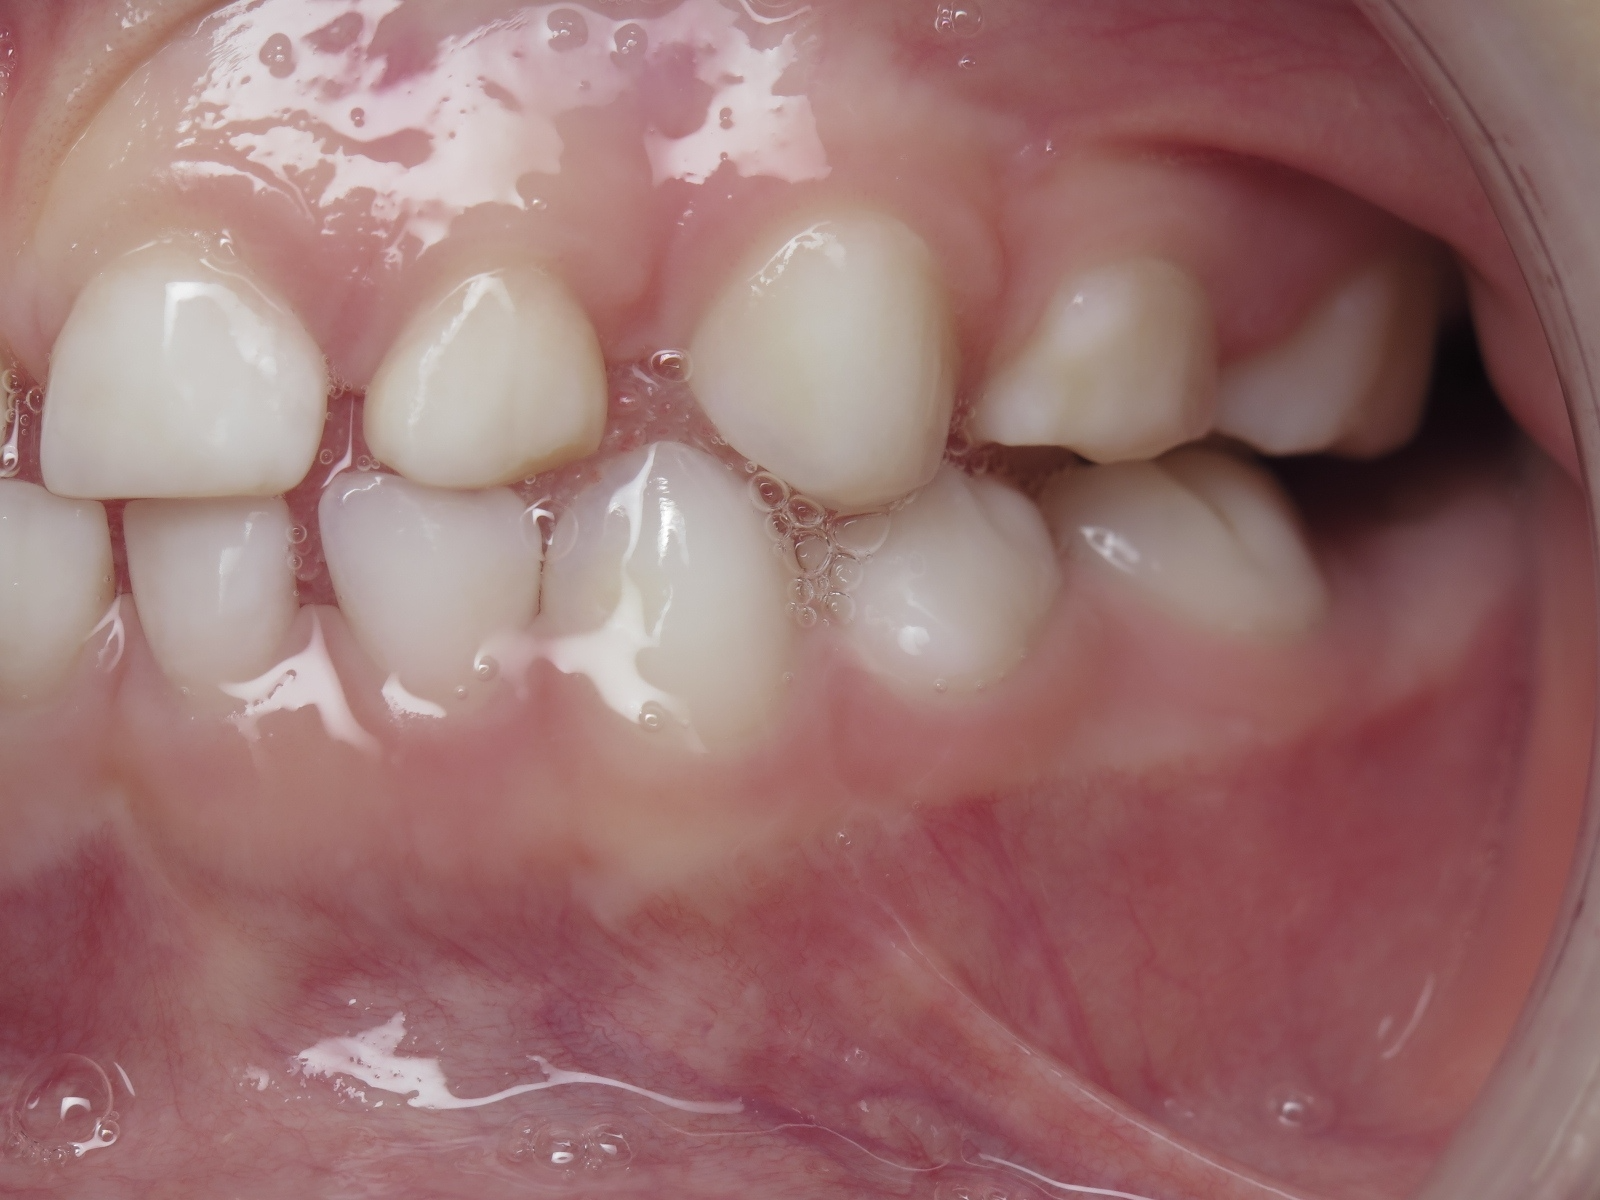

7.inversé droit 4 ans

inversion des dents postérieur coté droit

bilan début et en cours de traitement